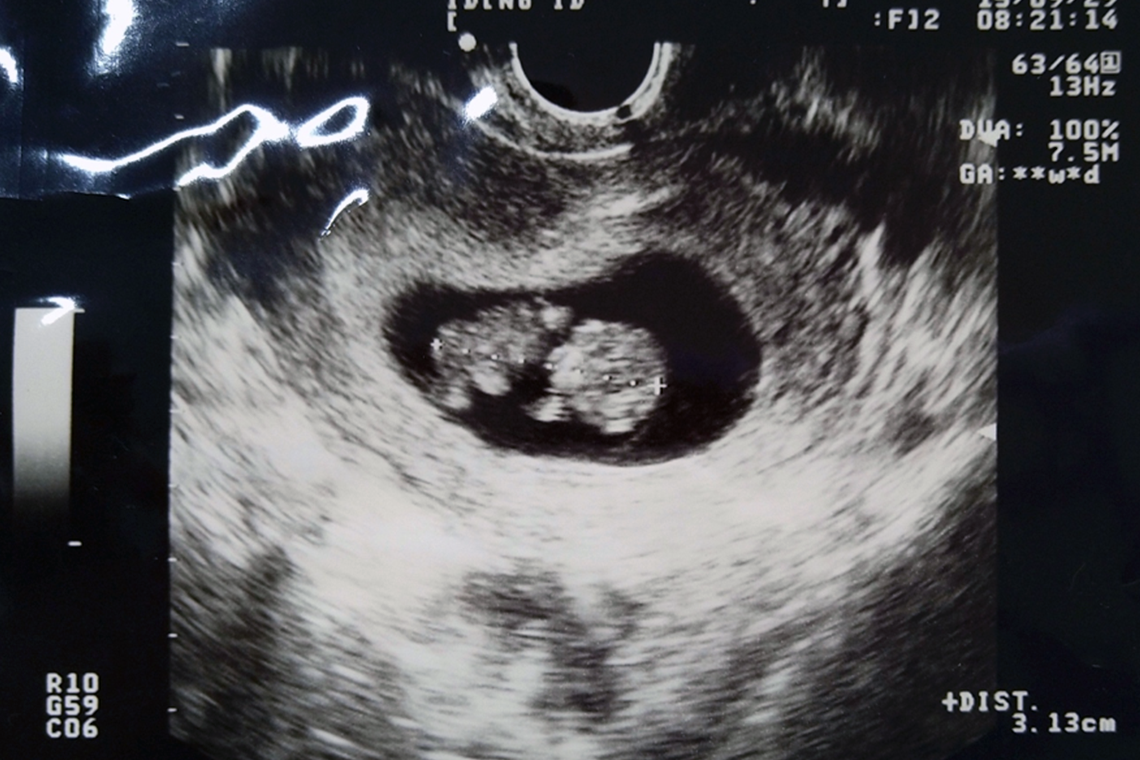

続いて野口さんが見せてくれたのは、妊娠9週目のエコー動画です。

「これは、お母さんのお腹の中にいる赤ちゃんです。9週目でまだ小さいけれど、ちゃんと心臓が動いているのが分かるかな?赤ちゃんの鼓動は1分間に約150回ととっても早いの。みんなも心臓の音を聞いてみましょう」